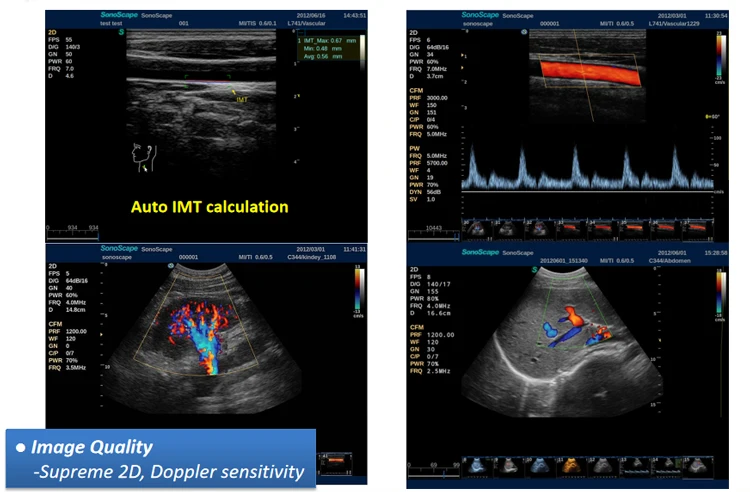

The S2 is configured with comprehensive functions, including complete scanning modes, such as outstanding 2D performance, sensitive blood flow, and 3D/4D imaging technology. The S2 is endowed with the best functions in its class! The scanning modes include B /2B/4B/M/ Steer M/Color/DPI/PW/ CW.